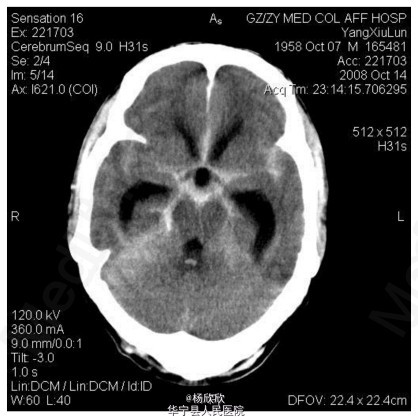

查体:T 39 ℃,BP 86/60 mmHg,球结膜充血,神经系统查体:颈强直。辅查:流行性出血热IgM、IgG阳性。实验室检查:白细胞 23×10^9 / L,血红蛋白166g/ L,血小板79×10^9 / L,尿素16.85mmol/ L,肌酐291umol/ L。入院1周后头颅CT提示双侧蛛网膜下腔高密度影。

查体:T 39 ℃,BP 86/60 mmHg,球结膜充血,神经系统查体:颈强直。辅查:流行性出血热IgM、IgG阳性。实验室检查:白细胞 23×10^9 / L,血红蛋白166g/ L,血小板79×10^9 / L,尿素16.85mmol/ L,肌酐291umol/ L。入院1周后头颅CT提示双侧蛛网膜下腔高密度影。